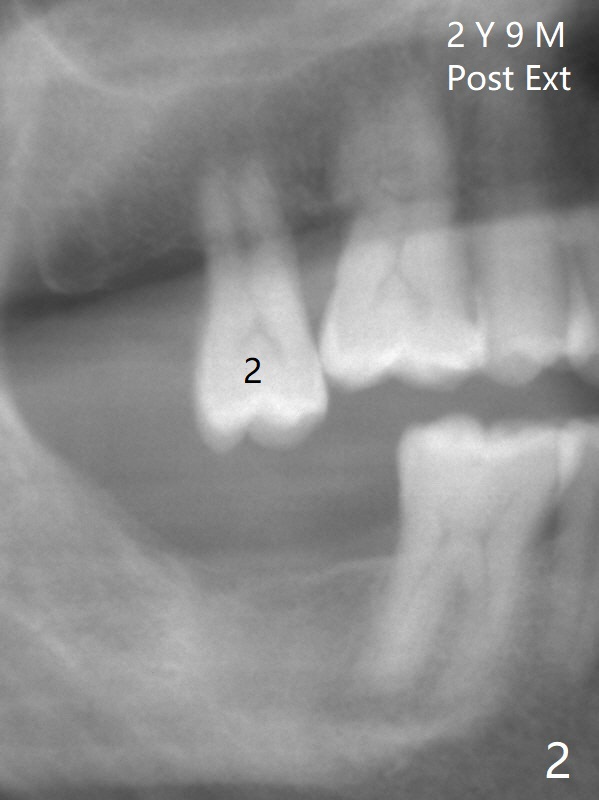

A 62-year-old man does not masticate on the right side due to facial paralysis (Fig.1 (pan taken ~ 8.5 years earlier)). Two years 9 months post #31 extraction, the tooth #2 has supraerupted (Fig.2). Nearly 7 years post extraction of #31 (Fig.3), the patient requests extraction of the supraerupted tooth because of repeated infection (Fig.4 distal view of the extracted tooth). There is calculus in the furca between the palatal (P) and buccal (B) roots. To facilitate bone regeneration in the distal surface of the tooth #3, Osteogen plug is placed in the distal portion of the socket of #2 (Fig.5 O), while allograft in the mesial one (*).